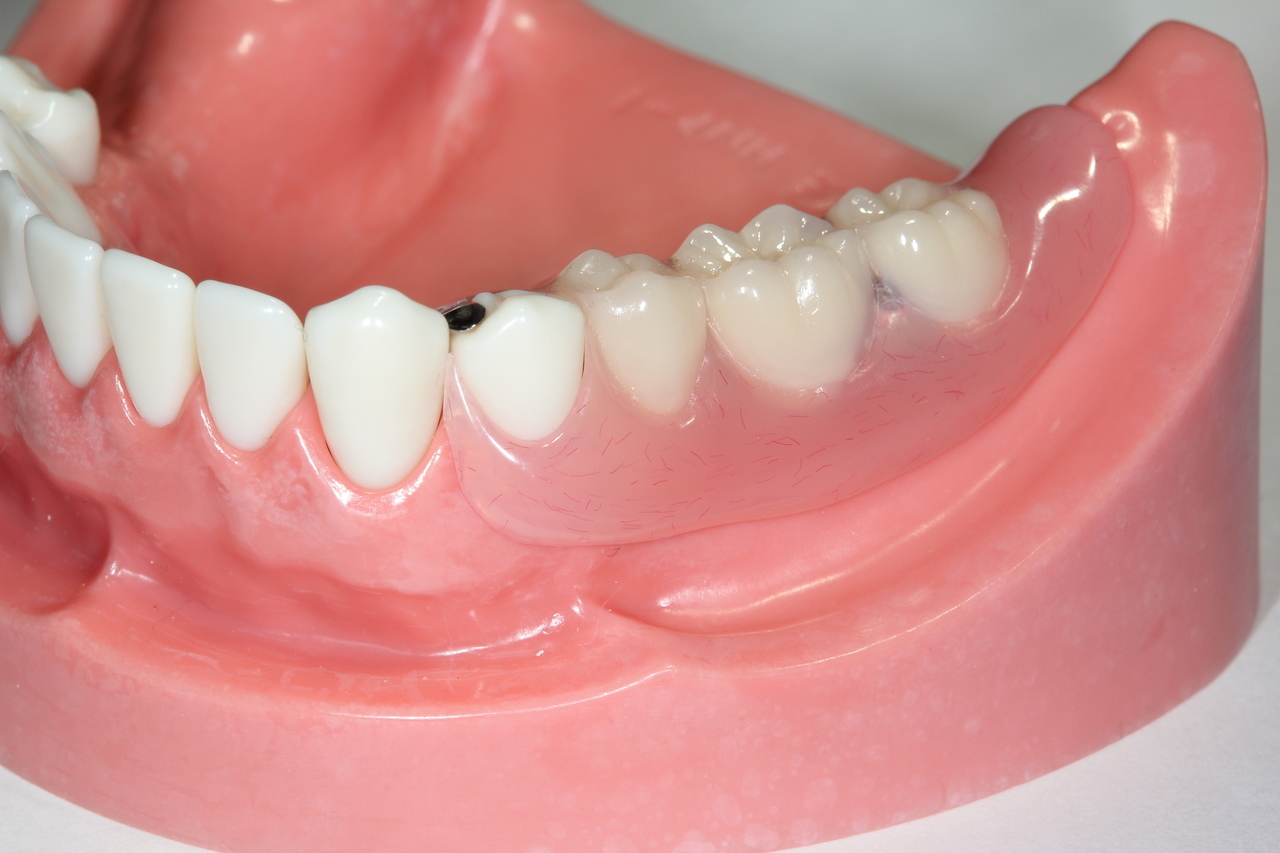

(通常のインプラント法)

歯科インプラントとは、歯を失った部分に人工歯根(主にチタン製)を外科的に埋め込み、その上にセラミックなどで作られた人工の歯を取り付けて、機能と見た目を回復する治療法です。

歯の欠損

歯を再生する時、インプラントは前後の歯に固定源を求めない唯一の治療法になります。自費治療になります。